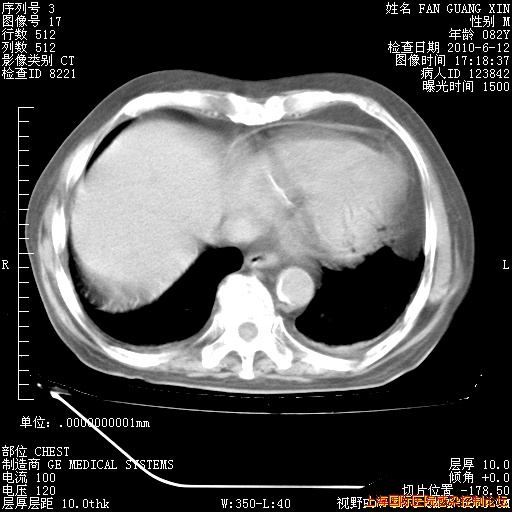

补发6月12日肺部CT肺窗

6月12日肺窗

6月12日纵膈窗